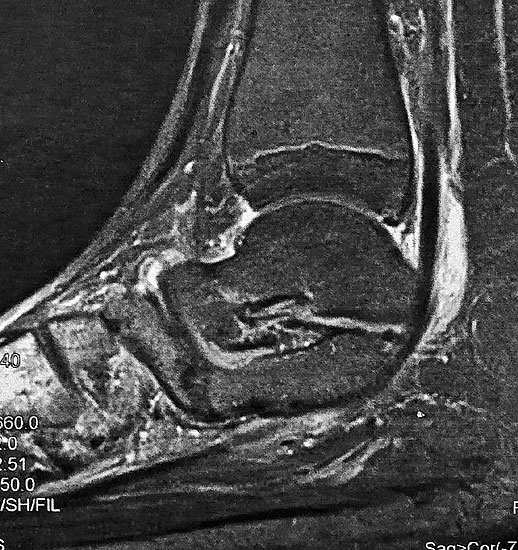

MRT und CT konkurrieren in der Fein-Darstellung der Knochenbrücke, der Beurteilung der nichtbetroffenen Anteile des Subtalargelenkes und der Sekundärveränderungen. Das MRT bietet den Vorzug, bindegewebige und knorpelige Strukturen (Abb. 2) und bei Einsatz von Kontrastmittel auch knöcherne Aktivierungsphänomene genau abzubilden; die knöcherne Feinstruktur und genaue Ausdehnung dagegen ist mit dem Dünnschicht-CT wesentlich exakter darstellbar (Abb.3). In manchen Fällen ist eine 3-D-Rekonstruktion des CT hilfreich. Besonders wichtig ist eine geeignete Schichtebenen-Wahl:

Die zweite wichtige Form tarsaler Coalitiones findet sich im medialen Bereich des Subtalargelenkes, am häufigsten unter Einbeziehung der medialen, mittleren Facette des talocalcanearen Gelenkes (Abb. 9). Die Ausdehnung der zunächst fibrösen, später zunehmend verknöcherten Brückenbildung kann sehr unterschiedlich Anteile der hinteren Kammer des unteren Sprunggelenkes mitumfassen; auch rein dorsomediale Formen ohne Einbeziehung der medialen Facette werden beobachtet (Abb. 2) 67 (Hamel 2008).

Diagnostisch sollte neben Röntgenübersichtsaufnahmen (indirekte radiologische Zeichen: Dorsaler Traktions-Osteophyt am Taluskopf, „talar beaking“; kontinuierliche Linie der Trochlea-tali-Kontur übergehend in die Sustentaculum-tali-Kontur, „C-Zeichen“ (Abb. 11) 10) immer die dreidimensionale Bildgebung eingesetzt werden. Das MRT (mit Kontrastmittel) kann die Struktur der Brückenbildung und z.B. die Qualität des Restgelenkes (Knorpel-Dicke) besonders gut abbilden; das Dünnschicht-CT zeigt die knöcherne Feinstruktur im Bereich der Coalitio und den oft sehr schrägen Spalt-Verlauf im Frontalschnitt dagegen häufig genauer. Meist findet sich die Überbrückung im Bereich der medialen Facette; die Schichten sollten jedoch bis weit nach dorsal beurteilt werden, da ansonsten dorsomediale Formen übersehen werden können. Rozansky et al 7 unterschieden fünf morphologische Typen auf der Basis von 3-D-CT-Rekonstruktionen. Allerdings ist eine prognostische Zuordnung bisher nicht möglich.